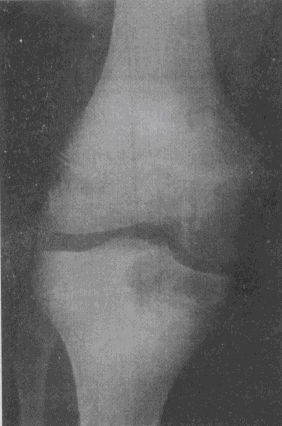

4.男,17岁。右膝关节疼痛1个月余,轻度肿胀。X线片示胫骨近端圆形骨质破坏(如图),应考虑的诊断是

A.骨囊肿

B.骨脓肿

C.骨结核

D.骨巨细胞瘤

E.成软骨细胞瘤

正确答案:C解题思路:骨结核大多数继发于肺结核。结核杆菌经血行到达骨或关节,停留于血管丰富的骨松质内而发病,病理上表现为渗出、变质和增殖。